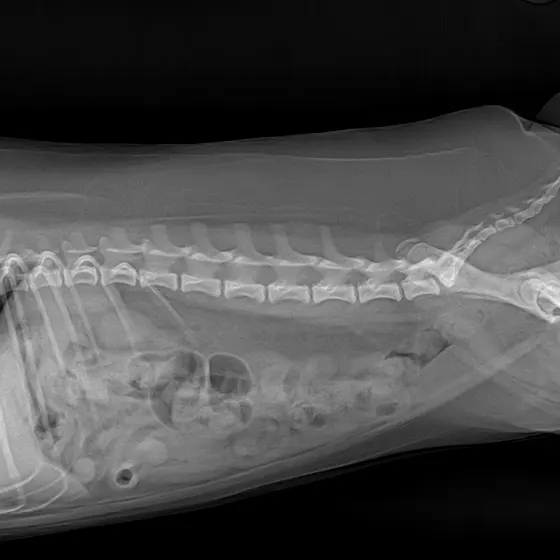

이 조그마한 녀석이 희귀병에 걸렸습니다

7번척추에 척수가 짧아서 아파합니다

서울대병원에서만 수술할수 있다네요

쓸개골도수술해줘야하는데 성장판이 안닫혀서 기다리다 이제야 닫혔다네요지금 쓸개골 4기가되어서 빨리해줘야하는데

일단 척추먼저 상담해보고 해야겠네요